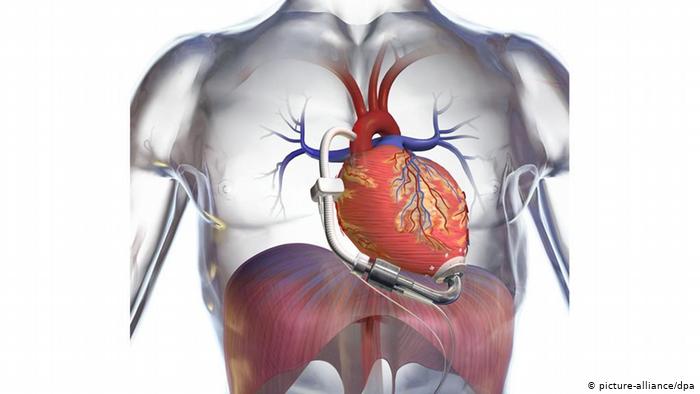

قلوب ومضخات دم اصطناعية

عندما لا يعمل القلب بصور منتظمة كما في حالة ضعف القلب، يتم الاستعانة بمضخة دم لتكمل عمل القلب ويتم زراعتها في الجسم، إضافة إلى ذلك يربط قلب صناعي لمساندة عمل القلب القديم في جسم المريض، أما المشغل الآلي والبطاريات الخاصة بالمضخة والقلب الاصطناعي فتكون في العادة خارج جسم المريض.

قلب اصطناعي قيد التطوير

وفي الوقت الحاضر يقوم العلماء بتطوير قلب اصطناعي يقوم بمهام القلب الطبيعي بالكامل، وتمت تجربة هذا القلب الاصطناعي الجديد بنجاح على الأبقار. يحتوي هذا القلب، كالقلب الطبيعي، على بطينين اثنين وأربعة صمامات. لكن ما زال أمام العلماء وقت طويل والكثير من الأبحاث لغاية تطوير هذا القلب الاصطناعي وجعله بديلا ناجحا عن القلب الطبيعي.